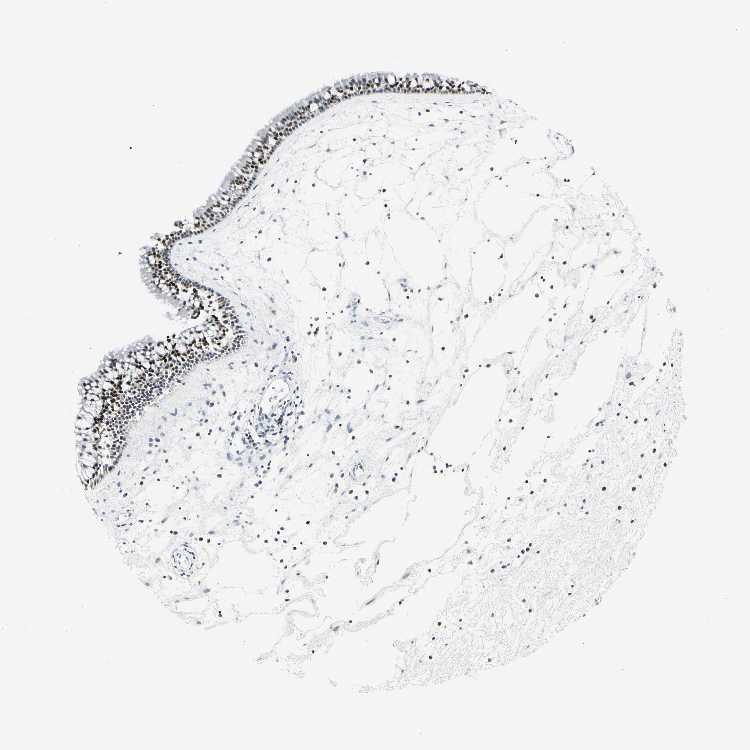

TISSUE PRIMARY DATA NASOPHARYNX Show tissue menu

NASOPHARYNX - Antibody stainingi

Antibody staining in the annotated cell types in the current human tissue is reported as not detected, low, medium, or high, based on conventional immunohistochemistry profiling in selected tissues. This score is based on the combination of the staining intensity and fraction of stained cells.

Each image is clickable and will lead to virtual microscopy that enables deeper exploration of all samples and also displays staining intensity scores, fraction scores and subcellular localization as well as patient and tissue information for each sample.

Antibody HPA006811Antibody HPA025820

Respiratory epithelial cells HighLow